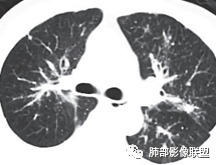

三、影像表现:左肺上叶多发片状高密度影,散在,边缘模糊,支气管壁稍增厚,中轴间质、小叶间隔增厚、有结节感,左肺上叶前段病灶可见胸膜增厚,部分小支气管不能分辨;右肺上叶后段混合磨玻璃结节,边界清,邻近胸膜凹陷;纵膈淋巴结肿大;心包增厚;左侧少量胸水。此外,扫及右侧胸腔内甲状腺肿;左侧肩胛骨旁肌群内脂肪瘤。

四、综合分析:老年男性,以咳嗽咳痰为主要临床表现,无发热,白细胞正常,影像表现为左肺上叶片影,前段结节影、胸膜增厚、部分小支气管不能分辨。左肺上叶中轴间质增厚、小叶间隔增厚、结节感,肺门纵隔见肿大淋巴结,尽管肺部病病灶边缘特征不典型,但高度疑及癌性淋巴管炎这一“次生灾害”却具有相当重要提示意义,而肺癌中最常伴癌淋的就包括腺癌。右肺上叶后段混合磨玻璃结节,边界清楚,张力明显,具有一定特征性,高度指向浸润性腺癌。这对于左肺病灶具有一定程度“助攻”效应。总体而言,本例左肺病灶的诊断关键点在于判断出癌性淋巴管炎。癌性淋巴管炎的结节在外围间质多见,小叶间隔可呈串珠状、结节状增厚,由于出血及水肿,小叶间隔增厚较明显,或呈不规则增厚。有的肺小叶呈多角状阵列。常合并胸水。

图1、2为同一病例,左肺下叶背段周围型肺Ca并左肺下叶局限型PLC,肿块与左下肺门间肺纹理不规则增粗,肿块与膈面有串珠样高密度影相连。图3为乳腺癌化疗后多发转移并弥漫型PLC,双肺多肺叶肺纹理不规则增粗增多并多发微小结节,其中右肺上叶后段肺纹理多呈典型的“毛刷征”,双肺上叶胸膜下区可见多发垂直于胸膜的不规则增厚的小叶间隔及微小结节。图4为右肺上叶周围型肺癌并弥漫型PLC,左肺上叶背段肺纹理不规则增粗增多呈典型的“毛刷征”,右侧叶间胸膜轻度增厚及多发微小结节。图5为胰腺癌术后多发转移并弥漫型PLC,双肺广泛肺纹理增多增粗并多发微小结节,双肺胸膜下多发肺小叶间隔增厚并见微小结节;图6(MPR冠状位)为食管癌术后肺弥漫型PLC,左肺广泛肺纹理不规则增多、增粗及多发小结节,边缘模糊。